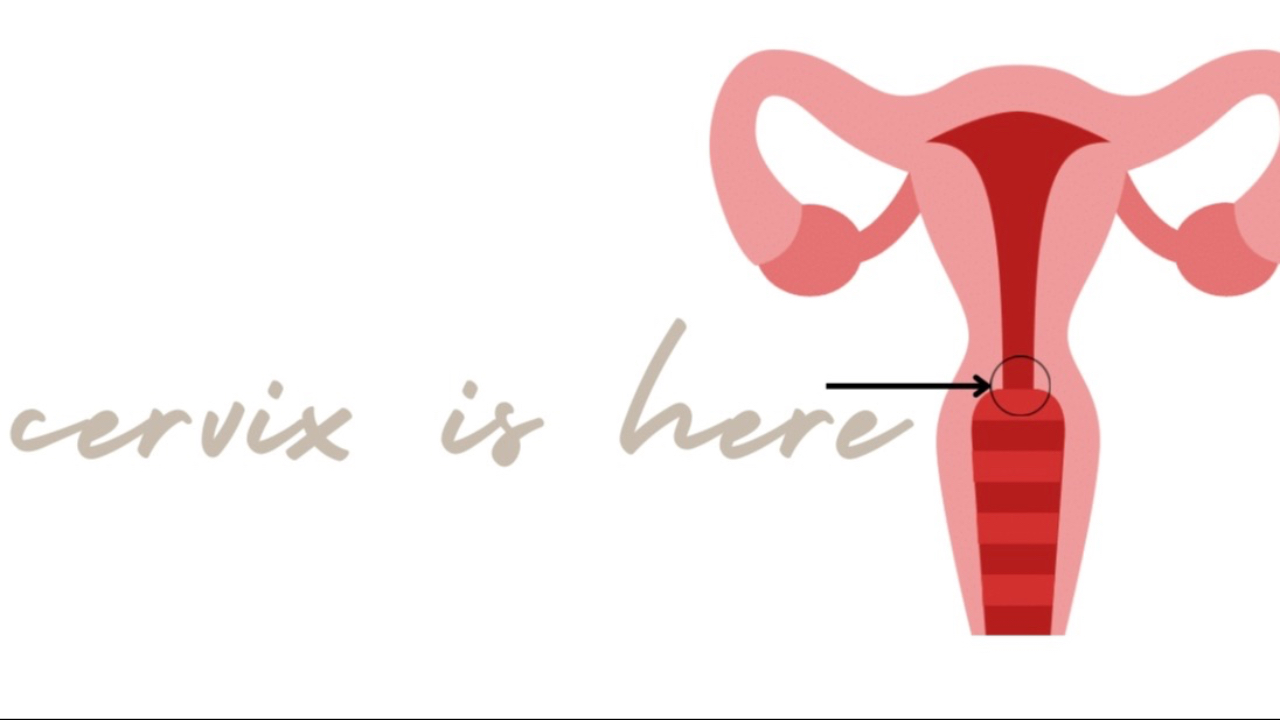

When you're pregnant, your body is doing all kinds of phenomenal things, and one part that deserves the spotlight is your cervix! You might not think much about it pre-pregnant, but this small and mighty part of your anatomy plays a huge role in your journey into motherhood; lets break it down an...